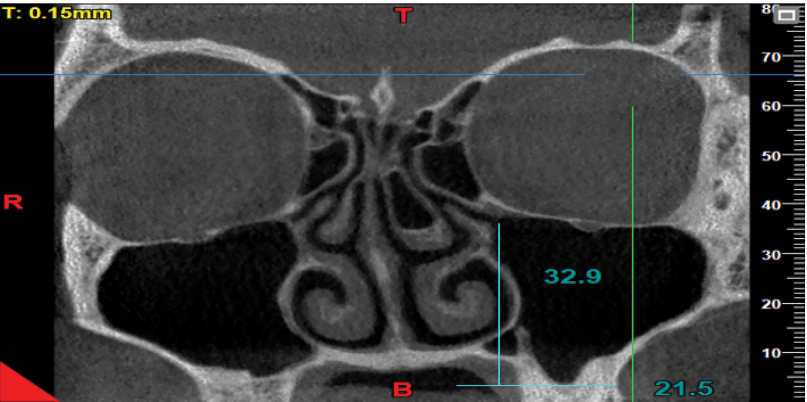

The axial, coronal, and sagittal views were used to assess the presence/absence of concha bullosa (Figure-1), and to measure the infundibulum length and ostium height (the most reliable and commonly used view to identify concha bullosa and make the measurements is the coronal view). The reviewed images visualized both the maxillary sinuses and the nasal cavity. Images with poor quality and those not visualizing the sinus floor, showing complete obstruction of the ostium, or lacking the middle concha were excluded. The patients’ age and gender, presence/absence of right and left concha, infundibulum length, and right and left ostium height were all recorded. The CBCT scans were evaluated by a board-certified oral and maxillofacial radiologist with 20 years of clinical experience. Subjectivity of the measurements was a source of bias in this study. To verify the reliability of the measurements, the intra-examiner reliability was calculated by repeating the measurements after a 3-month interval. The intraclass correlation coefficient was calculated to be 95%, indicating excellent intra-examiner reliability. To measure the dimensions of the drainage system, the infundibulum length and the ostium height were measured on both sides. For this purpose, the coronal view was scrolled to select the cross-section in which the uncinate process and the path of infundibulum and ostium were clearly visible, had an open path, and the largest values of the length and height were measured. The maximum length and height could be found on one or two different cross-sections. The infundibulum length was considered as the distance between the center of the ostium and the highest point of the uncinate process [3] (Figure-2). The ostium height was considered as the distance between the center of the ostium and the lowest point of the floor of the maxillary sinus [3]. To measure this variable, a line was drawn tangent to the lowest part of the sinus floor and parallel to the horizon. Next, a line was drawn perpendicular to the above-mentioned tangent line from the center of the ostium, and the obtained height was recorded (Figure-3).

Figure 3. Measuring the ostium height